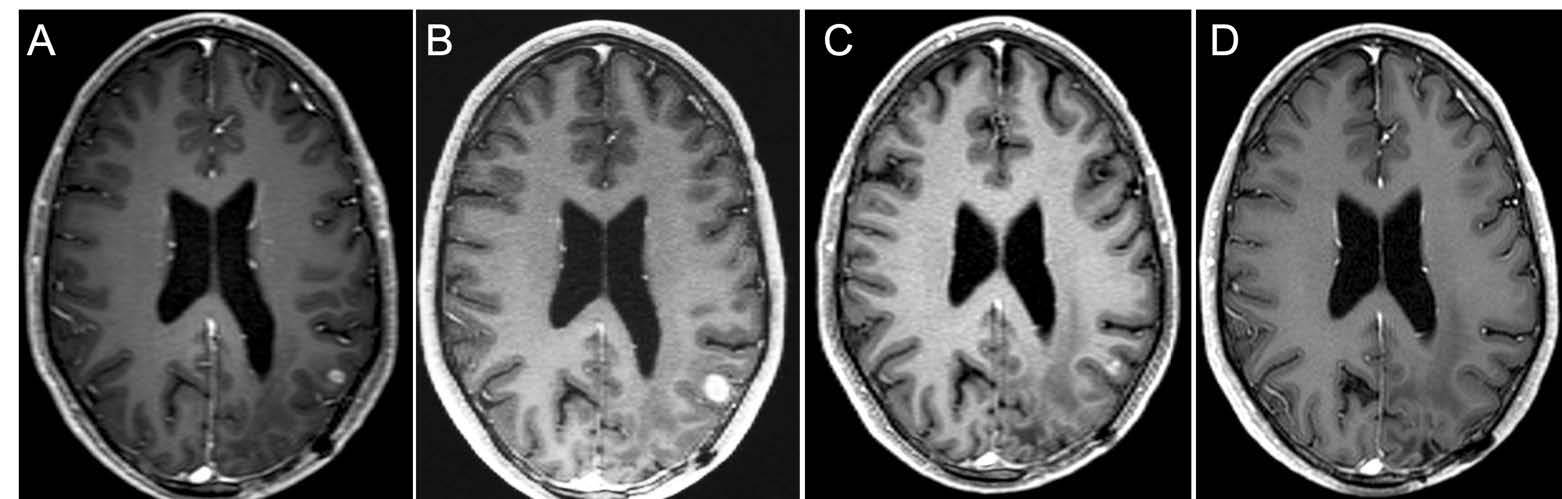

Magnetic resonance contrast-enhanced axial T1 images taken throughout the course of treatment for a 36-year-old man with IDH wild-type MGMT promoter methylated GBM

Columbia researchers led a clinical trial of selinexor, the first of a new class of anti-cancer drugs, which was able to shrink tumors in almost a third of patients with recurrent glioblastoma. The results of the international phase 2 trial were published in the January 10, 2022, issue of Clinical Cancer Research. The oral medication inhibits exportin-1 (XPO-1), a major exporter of proteins from the nucleus to cytoplasm that is overexpressed in many cancers, including glioblastoma. Selinexor was approved by the FDA for the treatment of refractory multiple myeloma and relapsed/refractory diffuse large B-cell lymphoma and had pre-clinical activity against glioblastoma models. The trial sought to identify the optimal dosing schedule and evaluate the safety and efficacy of selinexor in adults with recurrent glioblastomas whose cancer had progressed following initial treatment. Reduction in tumor size was observed in 28 percent of patients, and a tolerable dose was identified for future human trials already ongoing at Columbia and collaborating sites.

Magnetic resonance contrast-enhanced axial T1 images taken throughout the course of treatment for a 36-year-old man with IDH wild-type MGMT promoter methylated GBM are shown 7 weeks before selinexor (A), at baseline 1 week before selinexor (B), and during a partial response after 16 weeks of treatment (C), and then complete (D). Response beginning after 24 weeks of treatment and confirmed after 32 weeks of treatment (not shown).